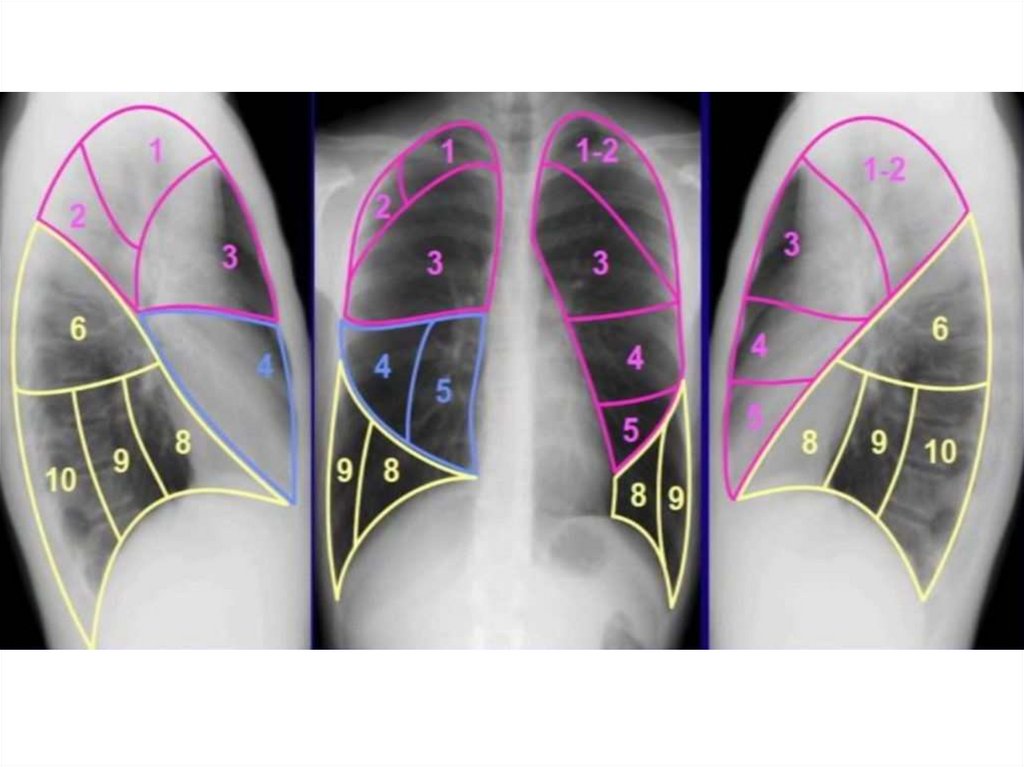

Анатомические изображения сегментов легких различных животных

Раздел: Другие животные